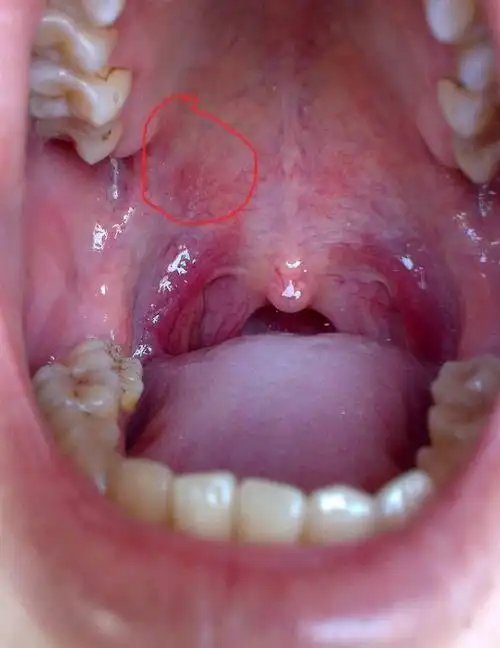

请问口腔上面长了个肉豆,像脸上很大的豆豆一样,注:本人经常长口腔

上颚长了一个疙瘩,不会痛,也不影响吃饭那些,请问这是口腔癌前病变吗?

口腔黏膜局灶性上皮增生